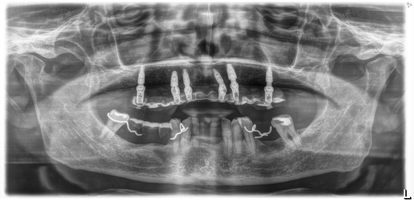

Full arch a carico differito arcata superiore